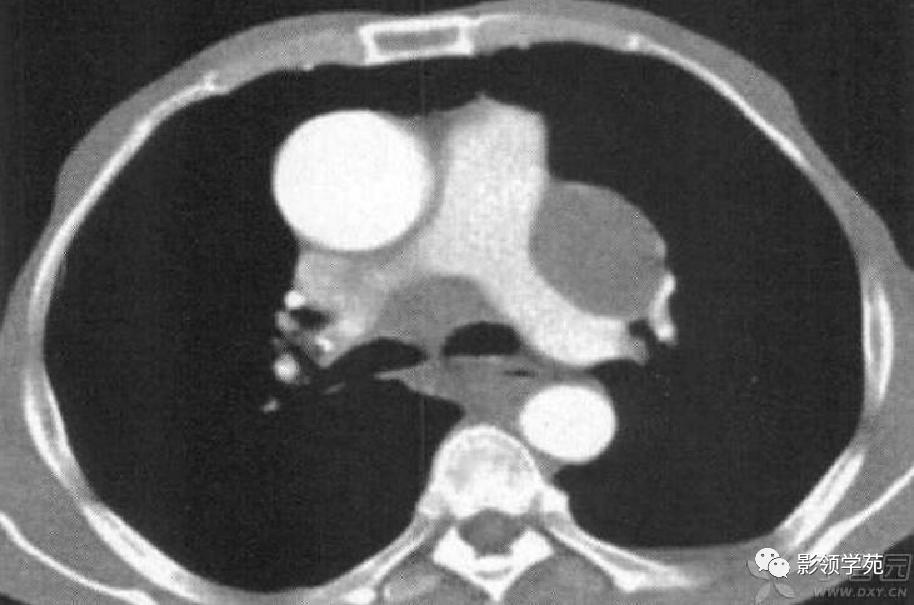

病例5:左下叶肺梗死,左肺下叶楔形病灶,边缘清楚,宽基底位于胸膜面,尖端指向肺门。

病例6:纵隔淋巴结增大。